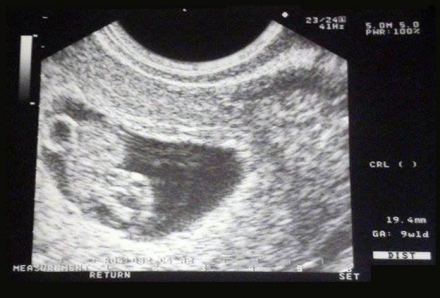

Terhesnapló 8. - Végre megvan az első ultrahang!

29-én leesett az első hó végre nálunk is, ezért gyönyörű hóesésben igyekeztem az orvosomhoz.

16 zseniális fotó a terhesség bejelentésére

Számos mód kínálkozik a nagy hír bejelentésére, többnyire aranyos ultrahangképekkel szokás jelezni a nagy hírt, azoban néhányan különösen vicces képeket hoznak létre ezért.